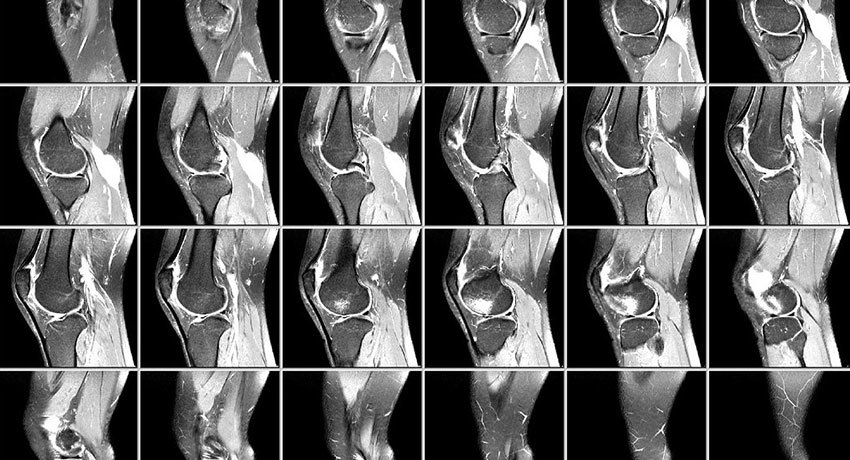

Во время МРТ применяют сильное магнитное поле. С помощью него аппарат создает изображения со «срезами» сустава и окружающих тканей в определенных плоскостях, трехмерные снимки.

На снимках МРТ коленного сустава хорошо видны сухожилия, связки, мышцы, хрящи и кости. Компьютерная томография не обеспечивает такой визуализации.

Затем врач МРТ оценит снимки и напишет заключение. Их нужно показать лечащему врачу — он установит диагноз и определит дальнейшую тактику обследования, лечения.